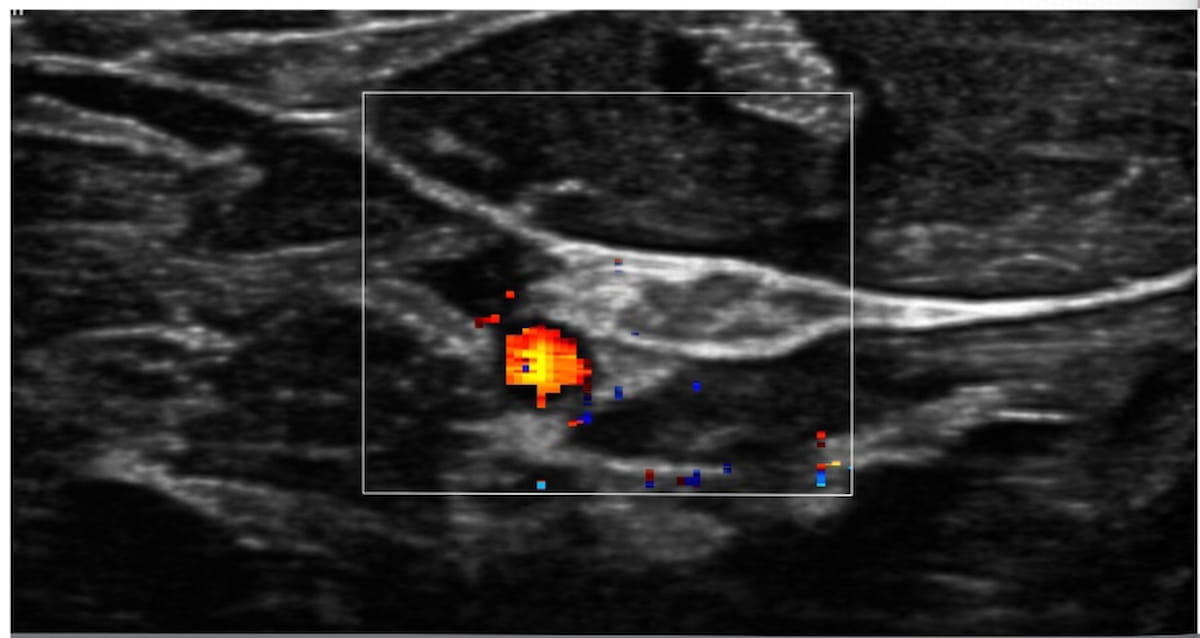

The newly FDA-cleared Fibroid Mapping Reviewer Application, which allows the creation of 3D uterus models from ultrasound images, reportedly facilitates diagnosis and interventional procedures for patients with uterine fibroids.

African American and Asian-Chinese women have a disproportionately higher prevalence of fibroids, according to newly published transvaginal ultrasound findings in a diverse population of nearly 1,000 women.